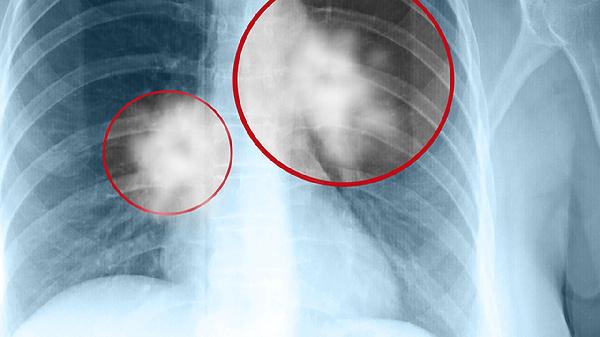

如何诊断实质性肿块:明确实质性肿块的性质需要借助医学检查。影像学检查如超声、CT或MRI可以初步判断肿块的大小、位置和形态。病理学检查如穿刺活检或手术切除后病理分析是确诊的金标准,能够明确肿块是否为肿瘤以及肿瘤的良恶性。血液检查如肿瘤标志物检测也有助于辅助诊断。